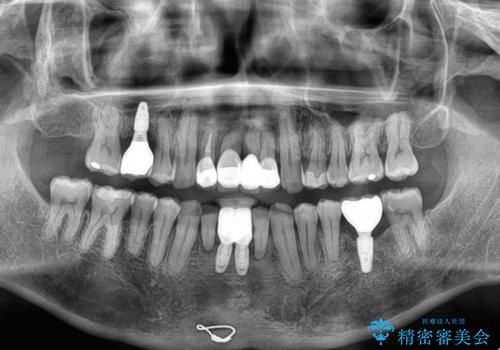

矯正治療を行いながら、欠損部はインプラントによる補綴治療を希望されたため、補助装置を用いたワイヤー矯正によりスペースを確保しながら歯列を整え、適宜インプラントを埋入していくこととしました。

下顎前歯にインプラントを2本埋入するのは非常に困難であり、どうしても歯肉位置に土台の金属色が見えてしまう仕上がりとなりました。無理をせずに1本のみの埋入とするか、ブリッジを提案しましたが、患者様の強い希望により、2本埋入することとなり、大変満足していただけました。